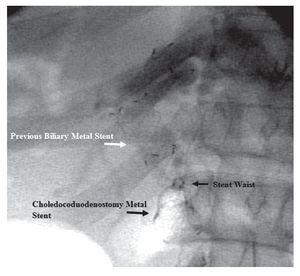

A 19-gauge FNA needle (Wilson-Cook Endoscopy, Winston-Salem, NC, USA) was used to perform a transduodenal puncture of the common bile duct through the proximal end of the biliary stent. Bile was aspirated and a cholangiogram demonstrated good filling of the right and left duct systems with no evidence of a stricture proximal to the puncture site (Figure 2). Under fluoroscopy, a 0.035-inch straight guidewire (Jagwire, Boston Scientific Corporation, Natick, MA, USA) was passed into the biliary tree and directed toward the hilum. Choledochoduodenostomy with a 10 mm x 60 mm partially covered self-expanding metal biliary stent (Wallfex®, Boston Scientific Corporation, Natick, MA, USA) was placed over the guide wire and deployed under fluoroscopy (Figure 3). Good bile and contrast efflux was seen (Figure 4).

¿ Figure 3. Radiologic image demonstrating proximal migration of prior biliary metal stent (white arrow) and the metal stent placed to create the choledochoduodenostomy fistula (black arrow) and also its waist because of the passage through the previous stent.